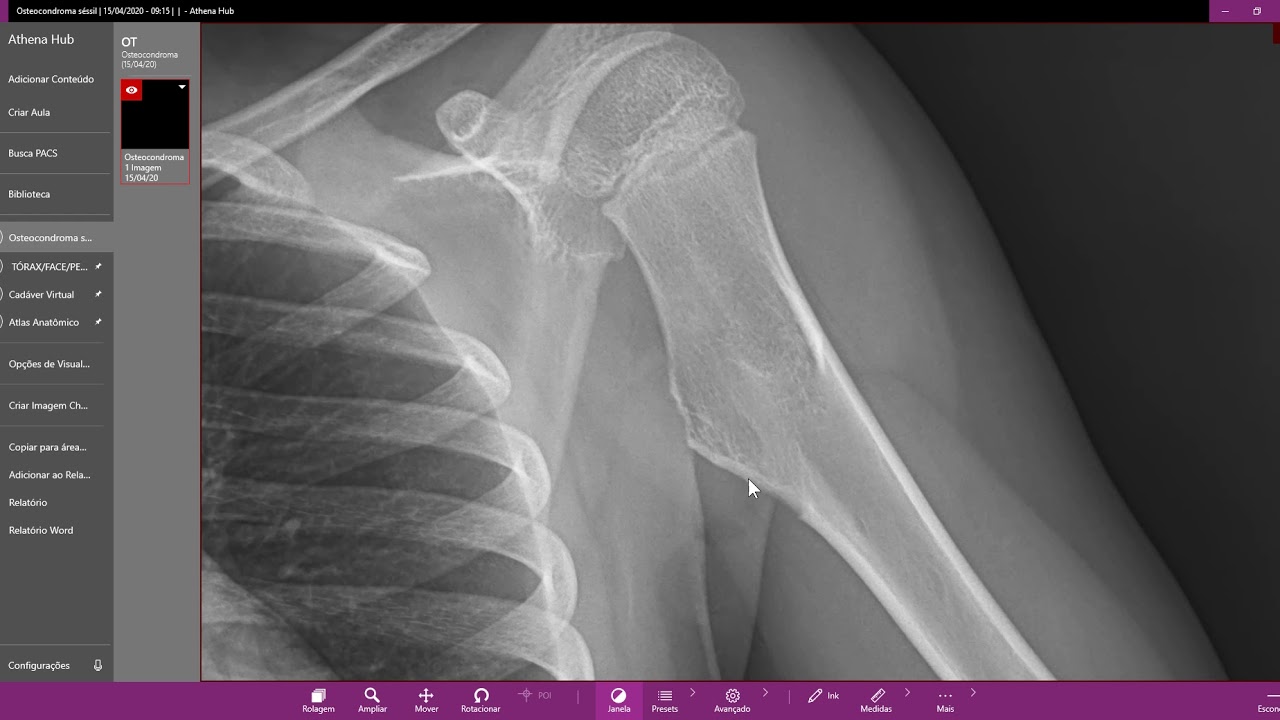

Olá meus amigos do vídeo de hoje é para explicar sobre o osteocondroma tomou Penido mais comum do osso que é diagnosticado principalmente na infância e na adolescência não tomou que tem predileção pela região metafisária próximo a cartilagem de crescimento principalmente em ossos longos como um profissional é uma proximal da tíbia proximal mais 90 porcento dos casos eles são solitários mas existe aqueles casos de desordem genética autossômica dominante que a exostose múltipla familiar Ou osteocondromatose é caracterizada pela formação de múltiplos ó shampoo não eles podem ser pede processo não sabe das vezes eles são assintomáticos mas

alguns deles podem causar complicações neurovasculares neuropatias compressivas pode causar deformidades que pode causar tendinites na inflamatório do simples nesse casa recepção cirúrgico está indicado é um tomou aquele para de crescer à medida que o mesmo também para de crescer pelo cresce em mim não é mesmo mas os casos que você já fez o crescimento penteado e passa atendo você faz o acompanhamento aquele tomou cresceu nesses casos nós temos que ficar com anteninha ligado que eu podemos estar diante de um processo de organização por causa de ação drama solitários esse processo que em torno 0900 oito

por cento menos de um por cento dos casos que já nos casos de exostose múltipla familiar esses serviços de uma organização pode pegar cinco porcento tá certo é grande abraço e até a próxima